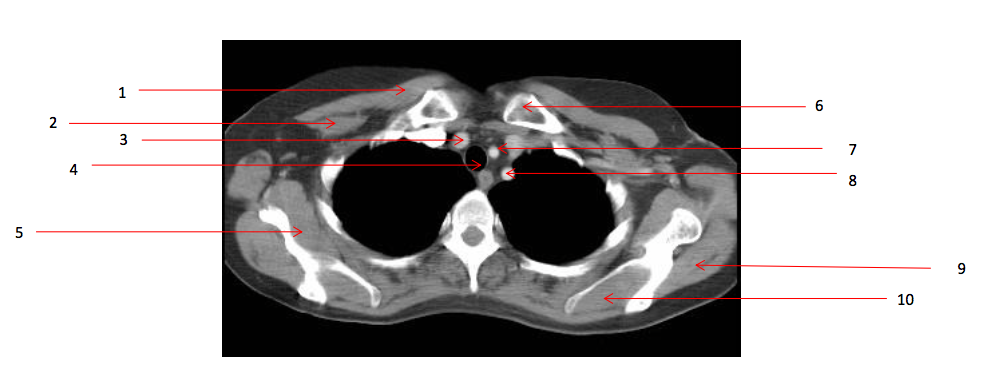

1

Number 2?

Rt pectoralis minor muscle

2

Number 6?

Lt clavicle

3

Number 10?

4

Number 1?

5

Number 8?

Lt subclavian artery

6

Number 4?

Trachea

7

Number 7?

Lt common carotid artery

8

Number 19?

9

Number 5?

Rt subscapularis muscle

10

Number 13?

11

Number 9?